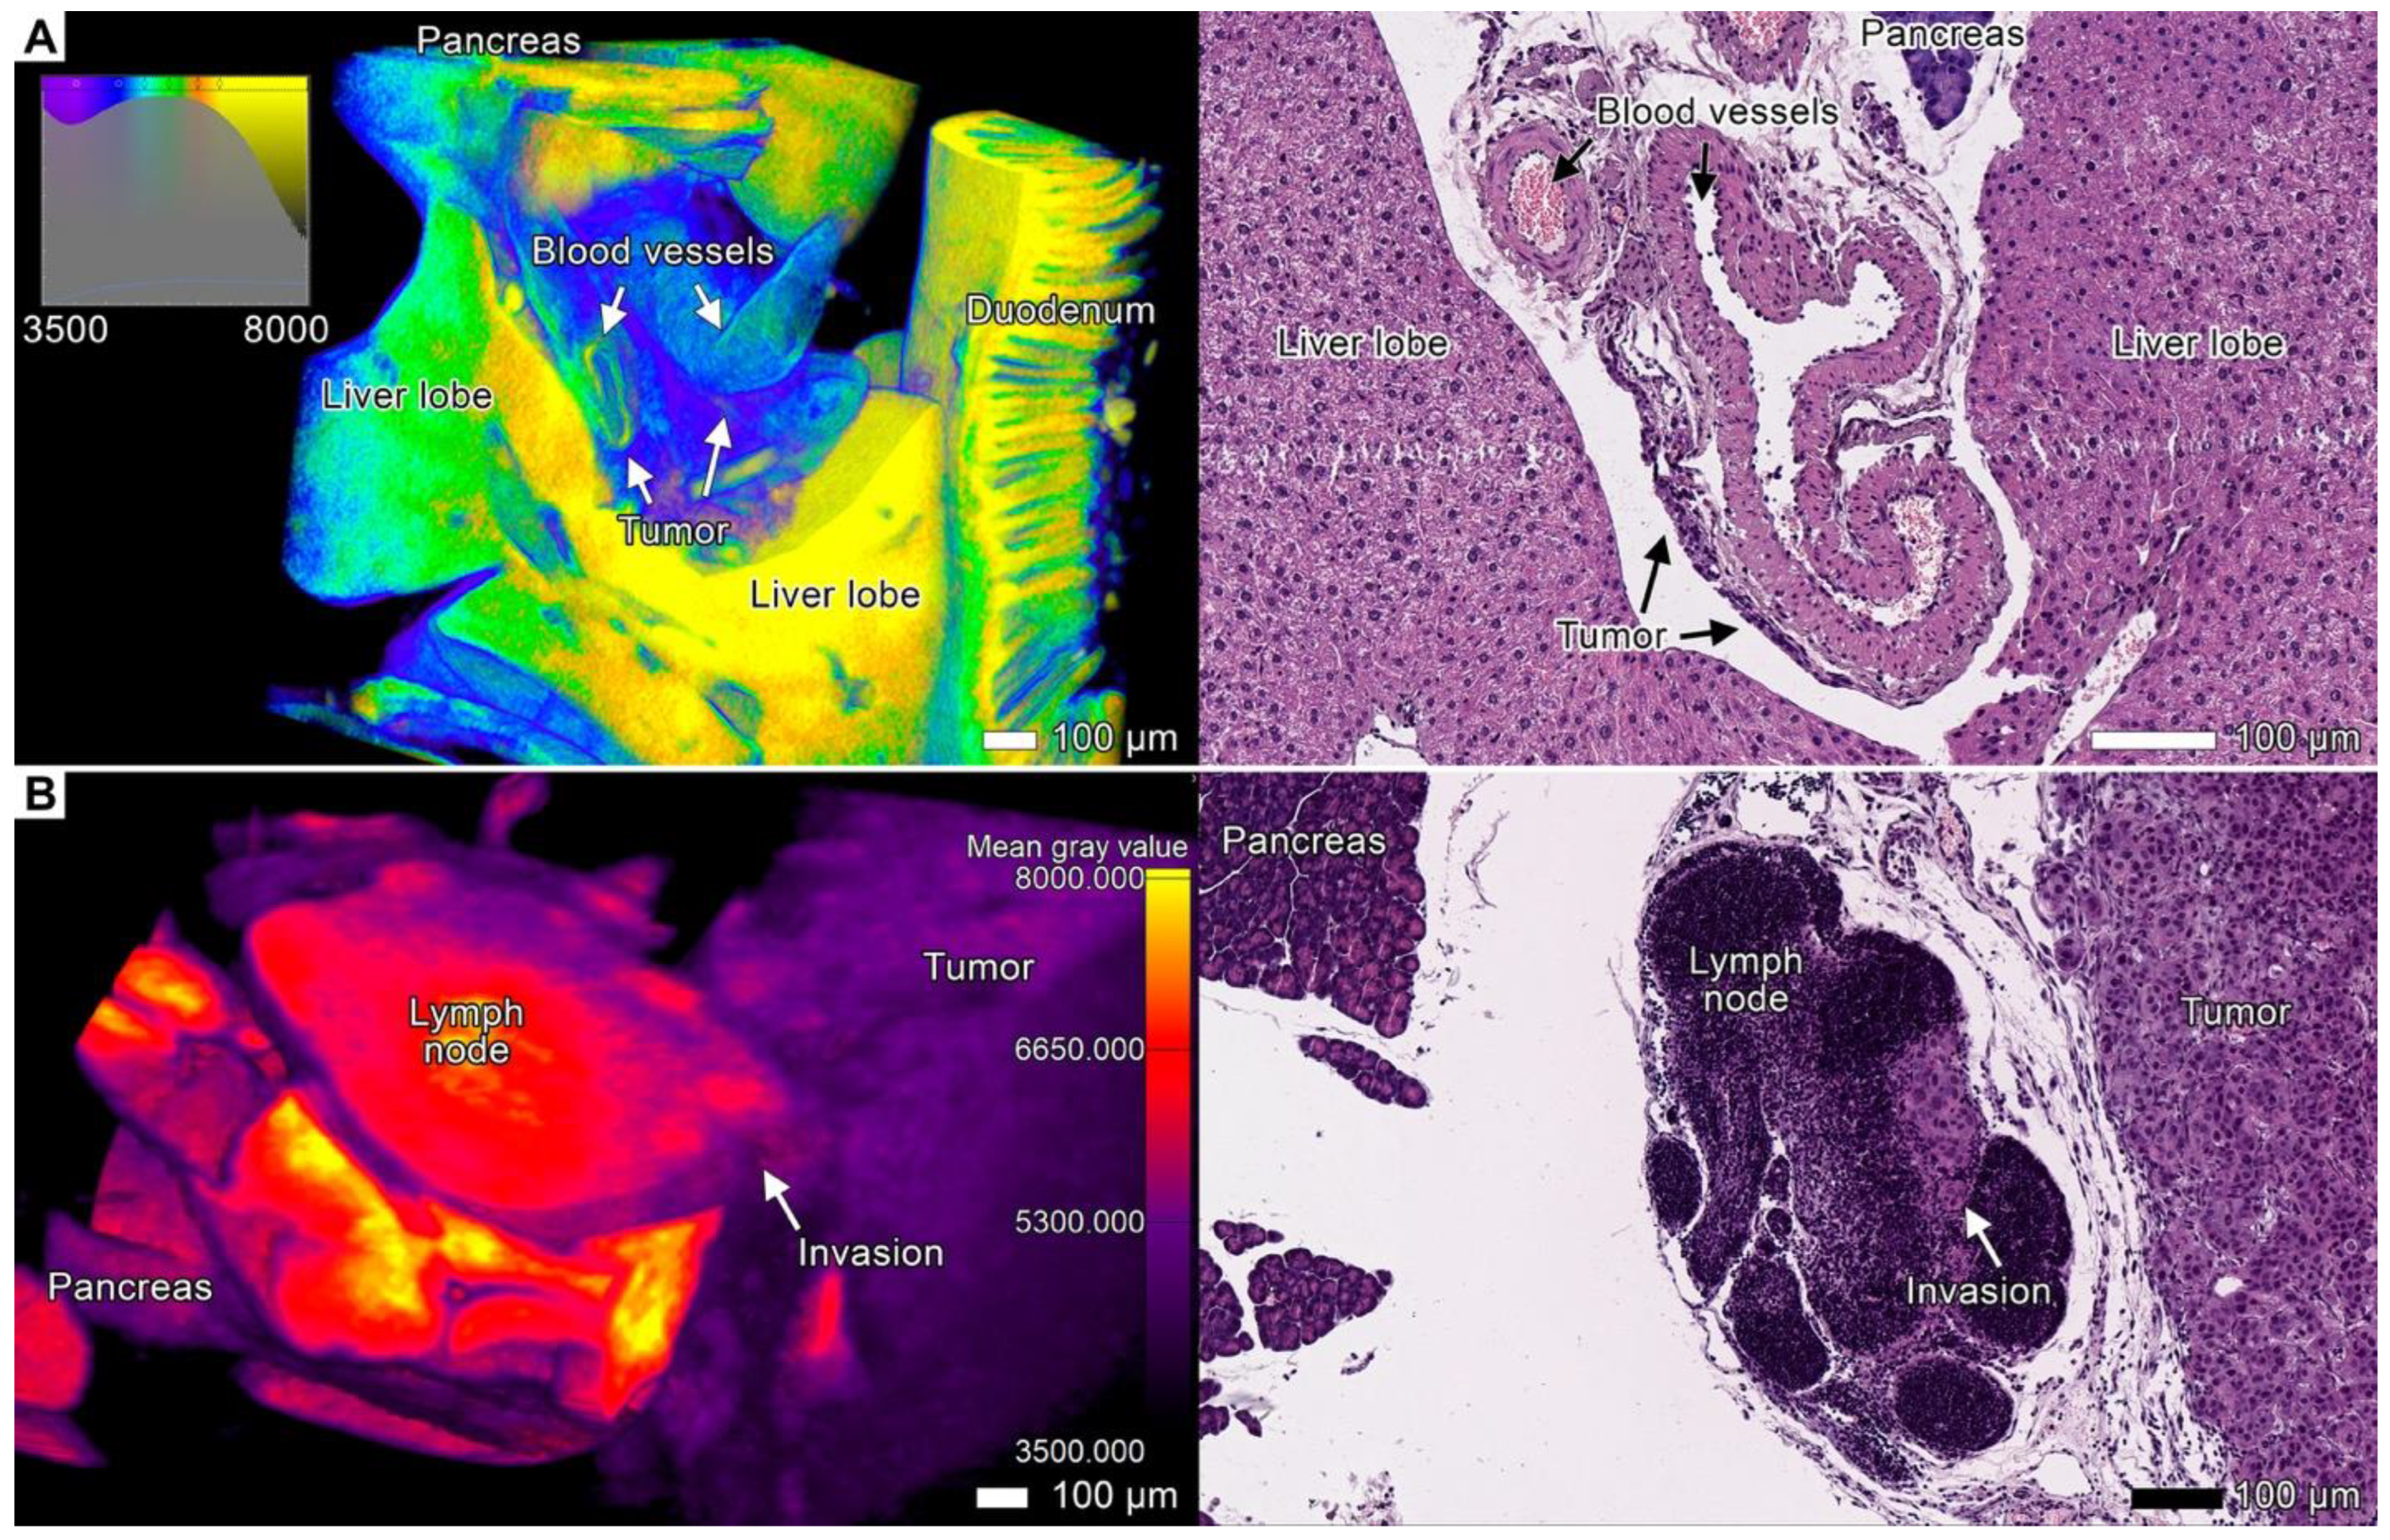

3.4. Tumor Invasion into the Pancreas

3.5. Tumor Invasion into the Liver